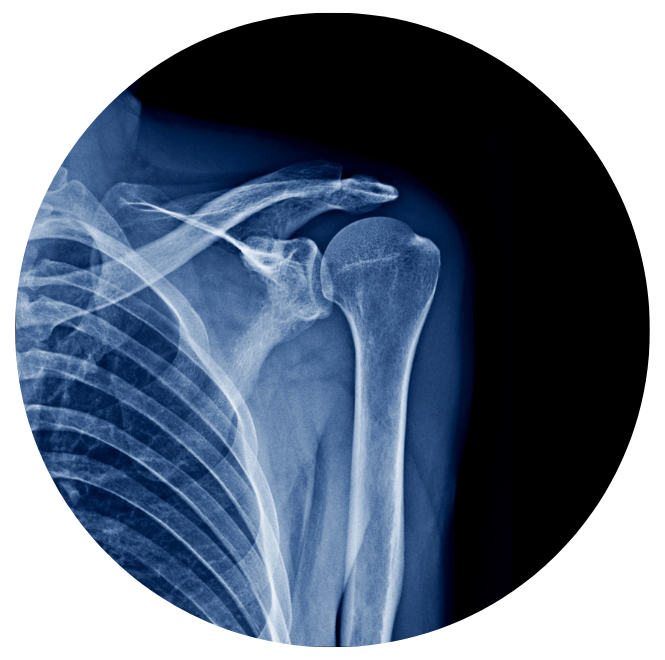

Por ejemplo, evaluar tus articulaciones con estudios adecuados, como una radiografía es un Smart Move.

Los paquetes Smart Bones* incluyen radiografías, consulta ortopédica y un plan de tratamiento para ayudarte a obtener un diagnóstico claro y actuar antes de que el dolor avance.